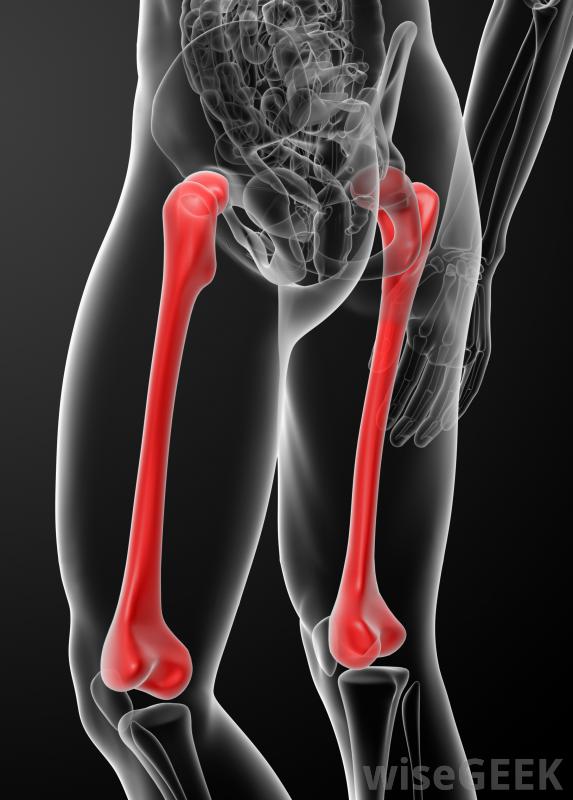

股骨头内钉有两种主要类型,顺行和逆行。顺行入路包括从股骨顶部或髋部插入股骨钉,而在逆行入路中,钉从膝盖端进入。顺行股骨钉是指治疗股骨干骨折最常用的方法,而逆行入路有时可用于更复杂的骨折,如肥胖患者,或者是多处受伤的人。

股骨是人体内最难折断的骨头。